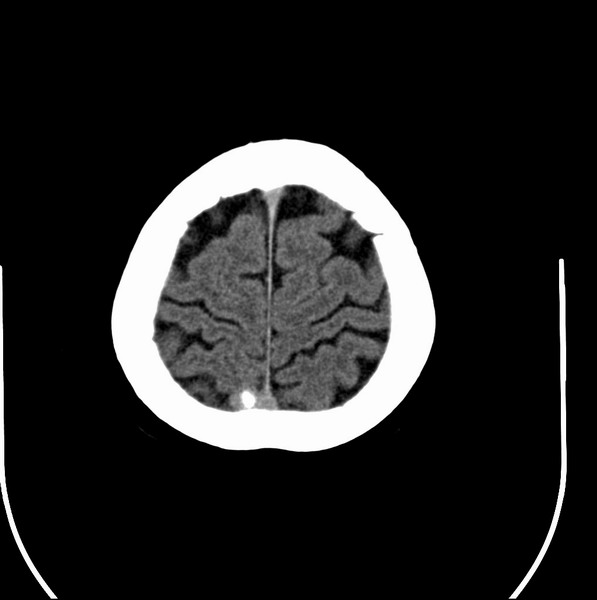

以下是引用余辉在2009-4-25 10:34:00的发言:[br]上矢状窦旁软组织肿块,内有钙化,与上矢状窦边界不清,灶后颅骨内板骨质增生硬化,支持考虑脑膜瘤,建议增强

以下是引用hmyj9在2009-4-25 14:21:00的发言:[br]病灶紧贴颅板处,中心高密度周围见软组织密度,局部颅板有增生,支持脑膜瘤诊断,建议增强。

以下是引用边生丽在2009-4-25 11:55:00的发言:[br][br] [br] 考虑脑膜瘤可能性大;建议行进一步检查。 [br] [br] [br]